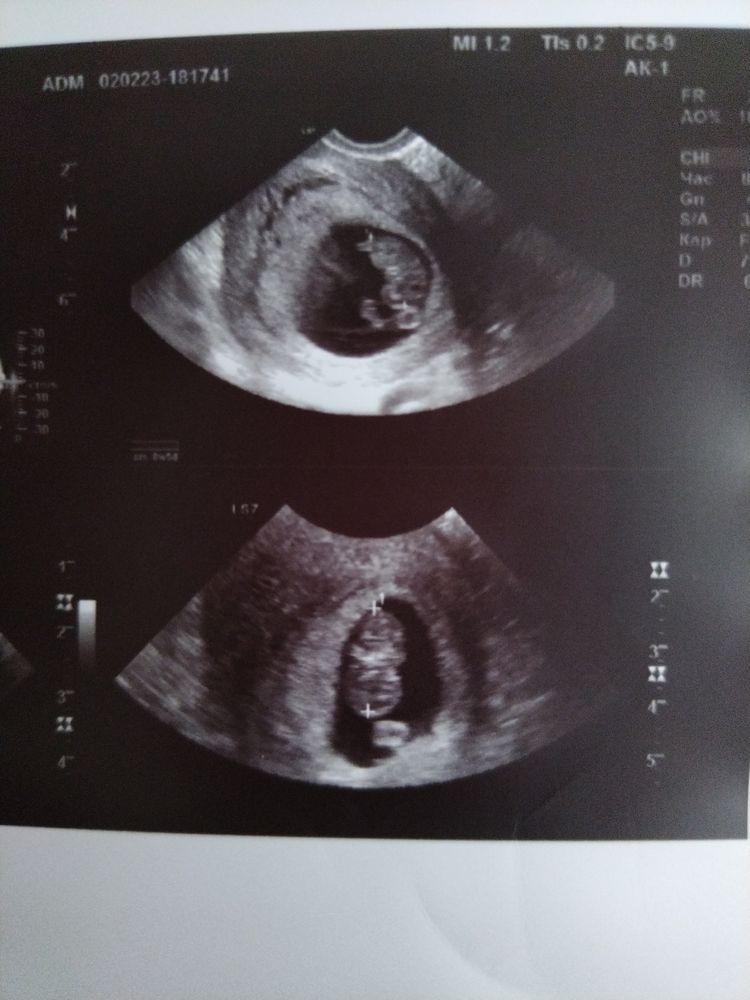

Страхи и переживанияДевочки подскажите пожалуйста?! Беременность 9недель 1день, пошла на узи вчера нашли отслойку небольшая сказали! У ребенка все нормально! Сердцебиение есть! У меня ни каких выделений нет! Назначили Дюфастон! У кого так было и чем закончилось?